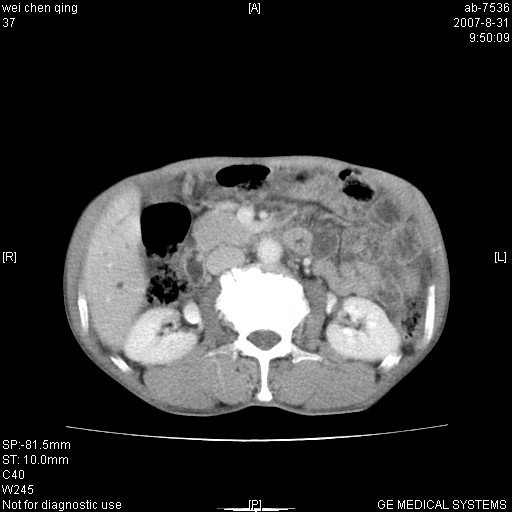

以下是引用zyyzzy在2007-8-31 14:34:00的发言:[br]该病人肝内胆管扩张,胆囊及胆总管未见明显扩张。在倒数第9层图像上可看到左右肝管结合部(肝总管)有软组织影,此处应薄层扫描。考虑肝总管占位(ca)、腹水。[br]